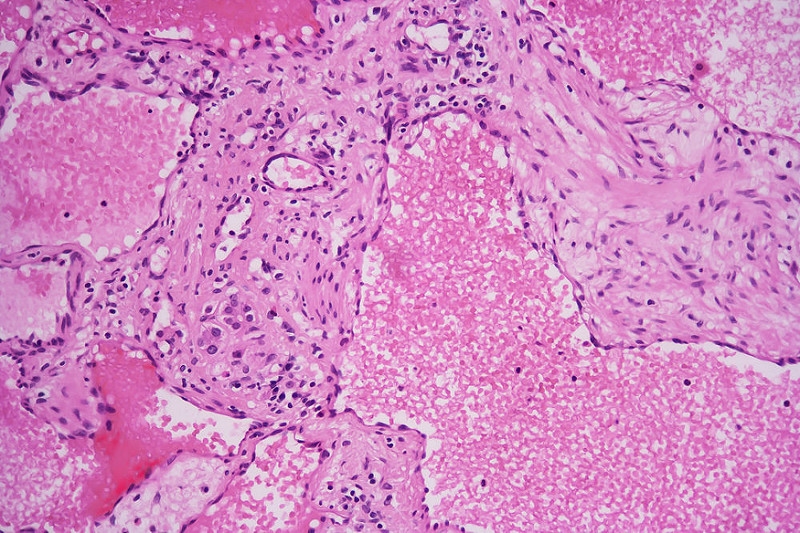

Abb. 3   Präparat eines kavernösen Hämangioms mit Leitz NPl 25/0.50  170/0,17

Abb. 4  Präparat eines kavernösen Hämangioms mit Leitz PL APO 25/0.65  160/0,17